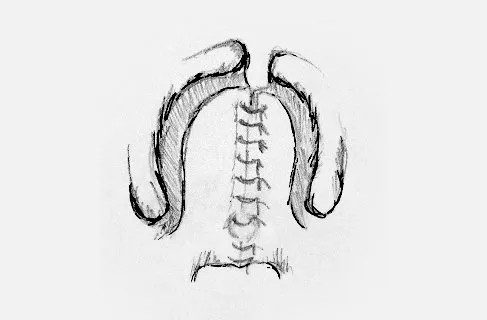

Cirurgia del Paladar. Palatoplàstia

El tancament es durà a terme apropant els laterals del paladar i fent la sutura a la línia mitjana. Al mateix temps, es realitza l'orientació de la musculatura dividida i l'allargament del paladar. Si cal, s'aprofitarà el temps quirúrgic per a la col·locació de drenatges timpànics per part d'ORL.

És normal l'existència d'una línia de punts de sutura al centre i que aniran desapareixent en les primeres setmanes. No ha d'alarmar la sortida d'aliment pel nas.